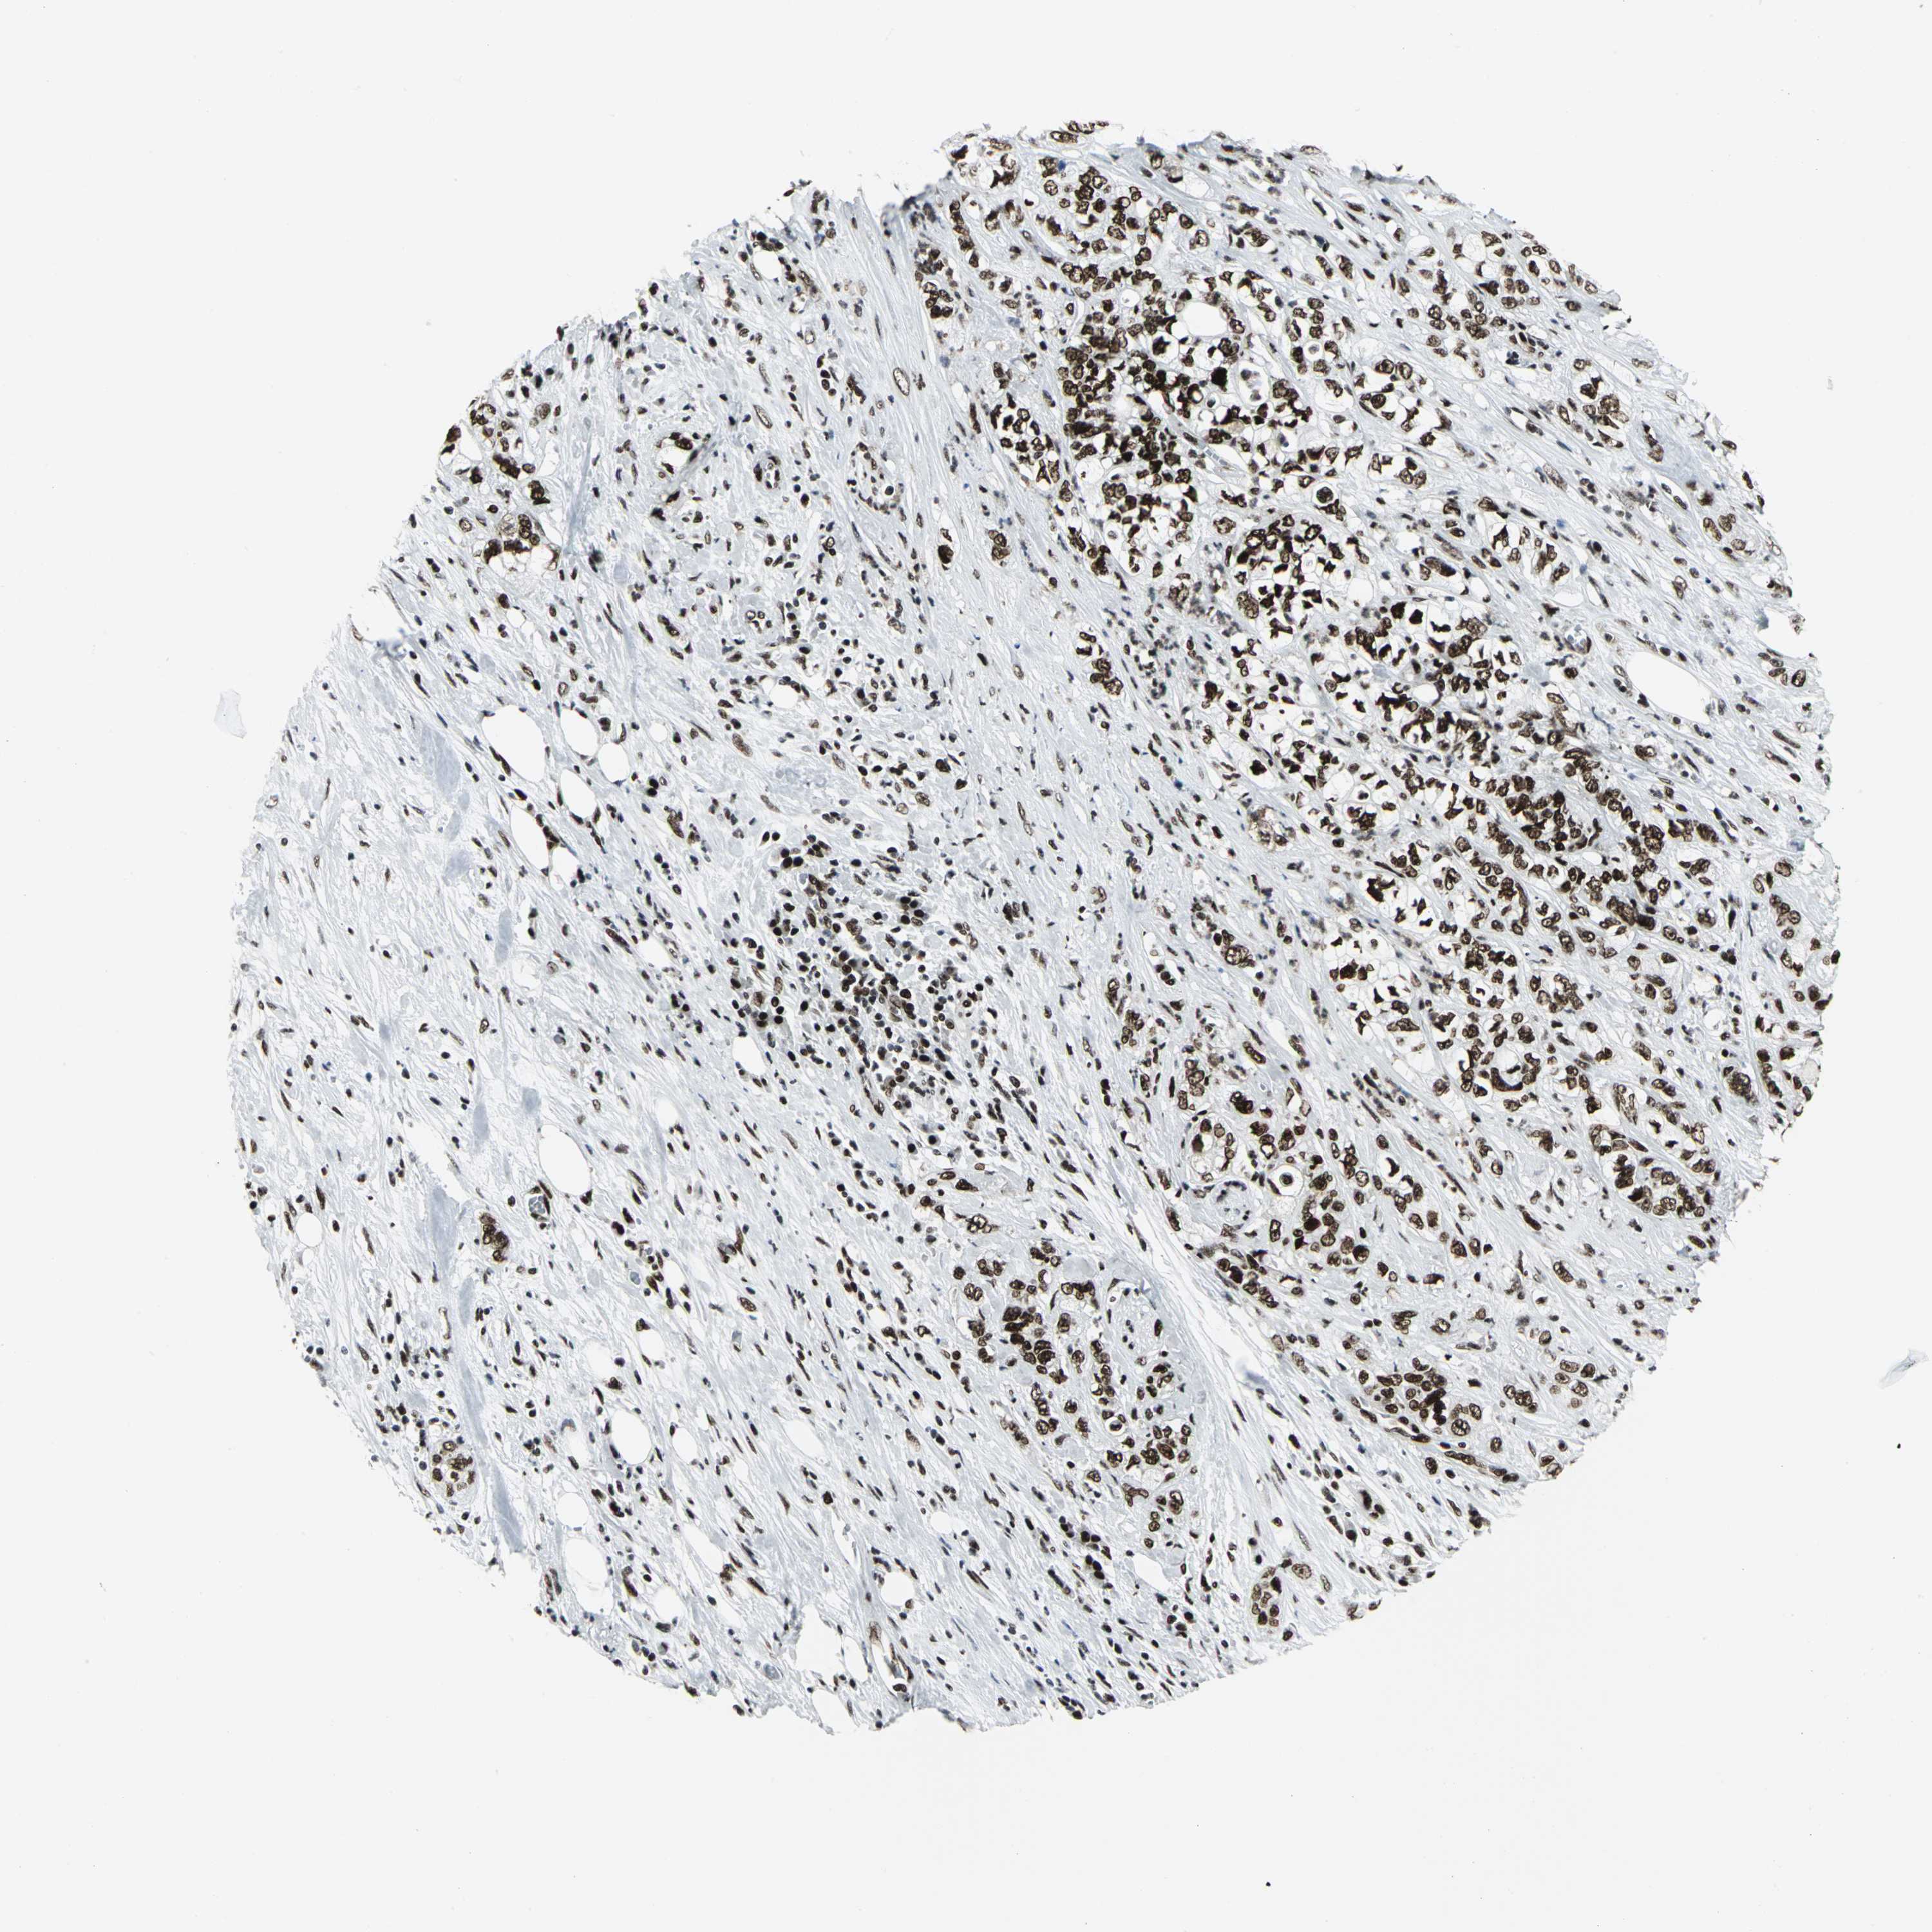

PANCREATIC CANCER - Protein expressioni

A mouse-over function shows sample information and annotation data. Click on an image to view it in a full screen mode. Samples can be filtered based on level of antibody staining by selecting one or several of the following categories: high, medium, low and not detected. The assay and annotation is described here.

Note that samples used for immunohistochemistry by the Human Protein Atlas do not correspond to samples in the TCGA dataset.

Antibody stainingi

Antibody staining in the annotated cell types in the current human tissue is reported as not detected, low, medium, or high, based on conventional immunohistochemistry profiling in selected tissues. This score is based on the combination of the staining intensity and fraction of stained cells.

Each image is clickable and will lead to virtual microscopy that enables deeper exploration of all samples and also displays staining intensity scores, fraction scores and subcellular localization as well as patient and tissue information for each sample.

Antibody CAB004208

Staining

High

Medium

Low

Not detected

Intensity

Strong

Moderate

Weak

Negative

Quantity

>75%

75%-25%

<25%

None

Location

Nuclear

Cytoplasmic/membranous

Cytoplasmic/membranous,nuclear

Adenocarcinoma, NOS

Adenocarcinoma, metastatic, NOS